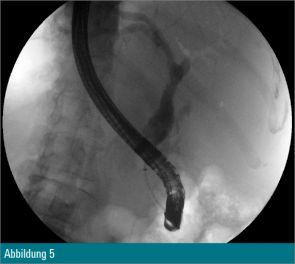

Trotz Fragmentierung des Konkrements (Abbildung 4) waren mehrfache mechanische Lithotripsien mit dem Dormiakörbchen in derselben Sitzung notwendig. Schlussendlich konnten alle Fragmente erfolgreich mit dem Ballon geborgen werden (Abbildung 5).